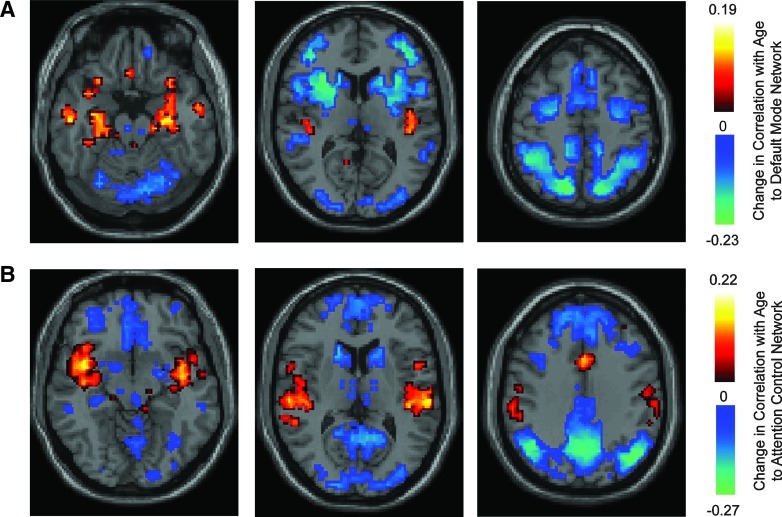

We evaluated the extent to which connectivity gradients between the default mode and attention control networks change during adolescence and early adulthood. For this purpose, we measured correlation between subject age (which ranged from 7 to 35) and correlation to the 2 networks for each of the 7266 brain regions. Significant changes in correlation with age are reported in Fig. 5 separately for the default mode and attention control networks, showing only results with significant change with age after false discovery rate correction for multiple comparisons at q<0.05.

FIG. 5.

Significant changes in correlation with age. (A) Significant correlation between age and correlation of each of 7266 ROIs with the default mode network, with acceptable false discovery rate q<0.05. (B) Significant correlation between age and correlation of each ROI to the attention control network. Color bars show units expressed as correlation (r), with only significant ROIs colored after multiple comparison correction. Negative values indicate decreasing correlation with age, and positive values increasing correlation with age. Slice locations: (top row) z=−20, 10, 55 (bottom row) z=−10, 10, 35.

With increasing age during adolescence and early adulthood, a clear pattern emerges that connectivity decreases between the attention control and default mode networks. The regions becoming significantly less correlated to the default mode network are specific to core hubs of the attention control network. Similarly, default mode regions almost exclusively comprise brain areas that become less correlated (more anticorrelated) to the attention control network during late neurodevelopment. A few regions also show significant increase in connectivity to each network with age. The medial temporal regions, including hippocampi and parahippocampal gyrus, become increasingly correlated with age to the default mode network, and the insula and anterior cingulate become increasingly correlated to the attention control network with age.

This result can be extended by considering both within-network and between-network connectivity across the age range we studied. Figure 6 illustrates changes in within- and between-network connectivity for each of the ROIs in the two networks. For default mode network ROIs, the more strongly connected an ROI was to the network, the more strongly its connectivity to the default mode network increased with age (r=0.57, p=0.8×10−72). This is consistent with a sharpening of the boundaries of the default mode network during development. The most strongly connected regions to the default mode network are located centrally within each hub where greatest anticorrelation is present to the attention control network. These changes with age effectively increase the magnitude of connectivity gradients to that attention control network across default mode network hubs. This can also be seen in Fig. 6B, where areas that are most connected to the default mode network also show the biggest decreases in connectivity to the attention control network with age (r=−0.6, p=0.5×10−81).

A different pattern emerges with increasing age in the attention control network. ROIs within the frontoparietal hubs of the network that are most connected to the attention control network do not show increased connection to the network with age. Rather, almost all of the frontoparietal ROIs show slight decreases in within-network connectivity with age. Instead, there is increased connectivity between the anterior cingulate and insular hubs of the network with the rest of the network. ROIs that showed the highest correlation to the default mode network showed the greatest decreases in connectivity to the attention control network (r=−0.71, p=0.2×10−96). This change also helps generate the decreasing correlation between the two networks with age illustrated in Fig. 5 and serves to increase connectivity gradients between the two networks.